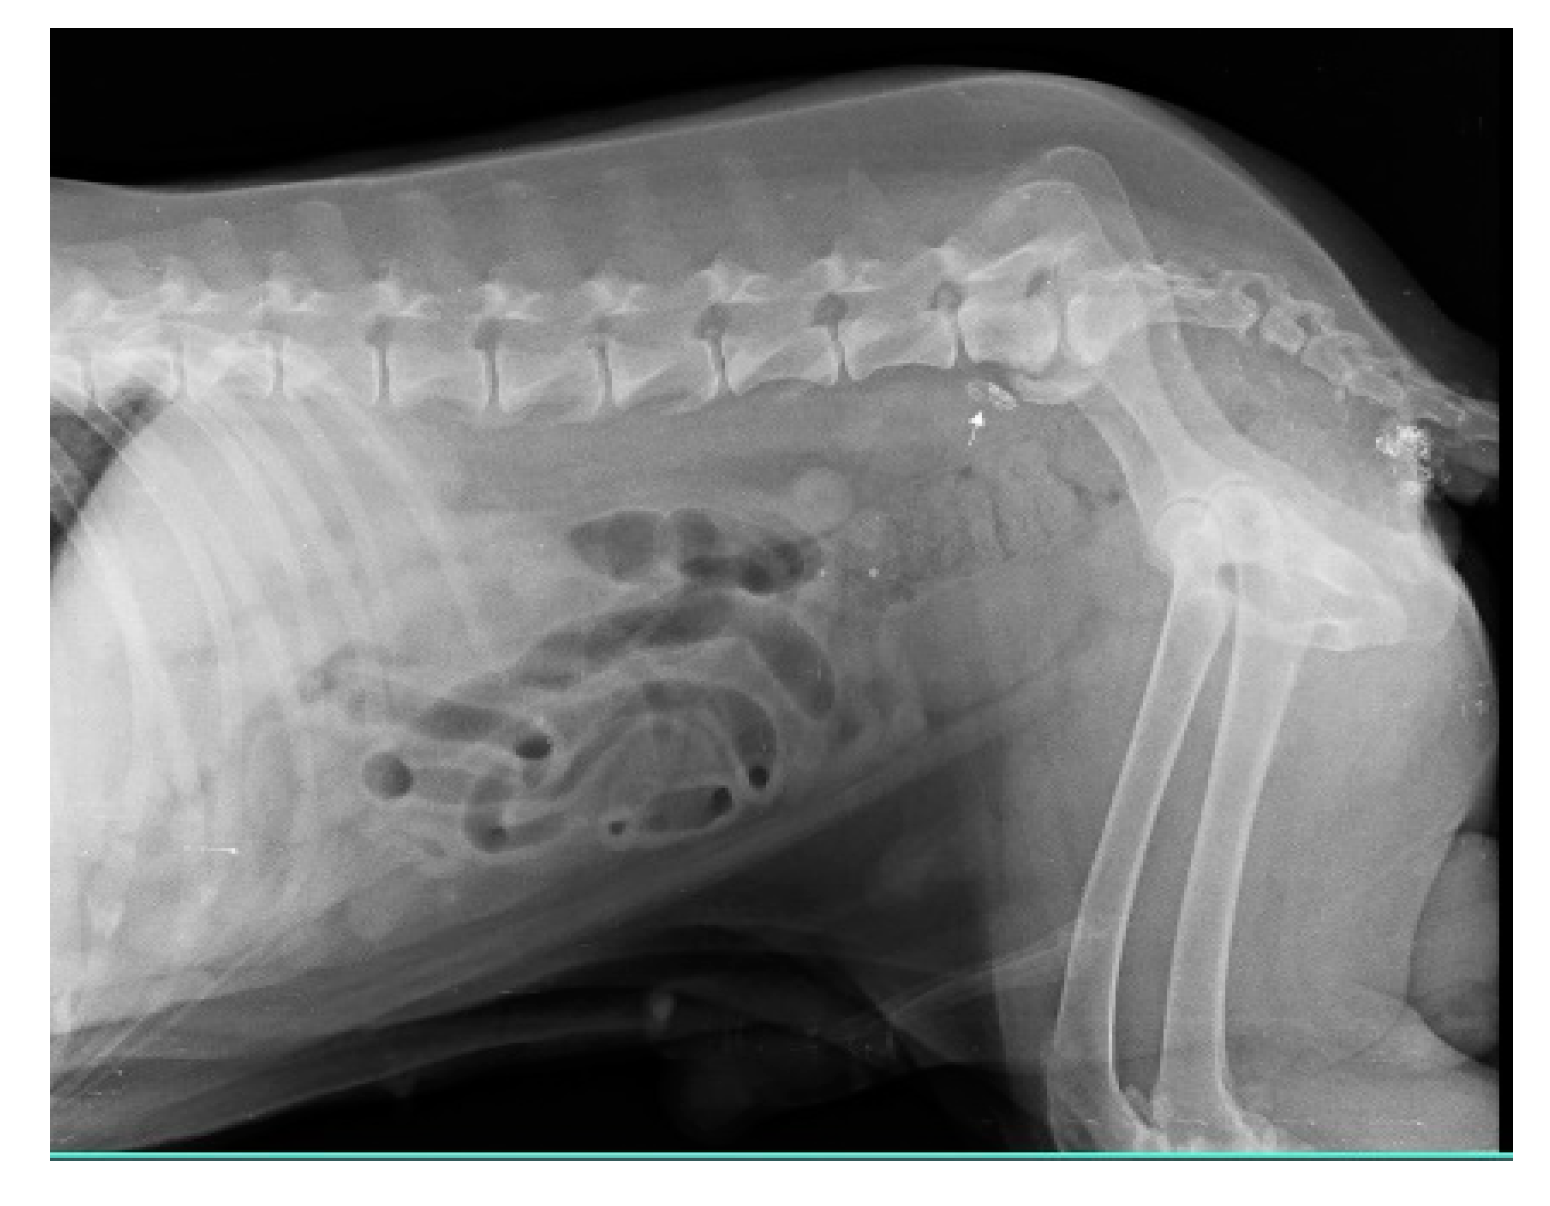

In multicentric lymphosarcoma (n=6), within minutes of peritumoral and intradermal injection of iohexol in popliteal LN, deep inguinal LN and miLN were discovered as SLN as shown in Fig. 9.

Figure 9. Lymphatic channel from popliteal lymph node to inguinal lymph node and then to medial iliac lymph node (solid white arrow) in multicentric lymphosarcoma.

Preprints 77141 g009

The malignancy criteria of the peripheral LN (submandibular, parotid, cervical, axillary, inguinal, and popliteal LN) were clearly described by ultrasonography. These criteria include oval form with S/L ratio 1, peripheral and central vascularization, and hypoechoic nodes as shown in Fig. 10, which are confirmed by cytology and biopsy. In the case of a primary tumor mass (lymphoma at 3rd molar) in the mouth cavity, mandibular LN were recognized as SLN within 2 minutes of indirect CT lymphography with iohexol. All superficial LN were found to have metastasized in lymphosarcoma which was a poor predictor of survival time.